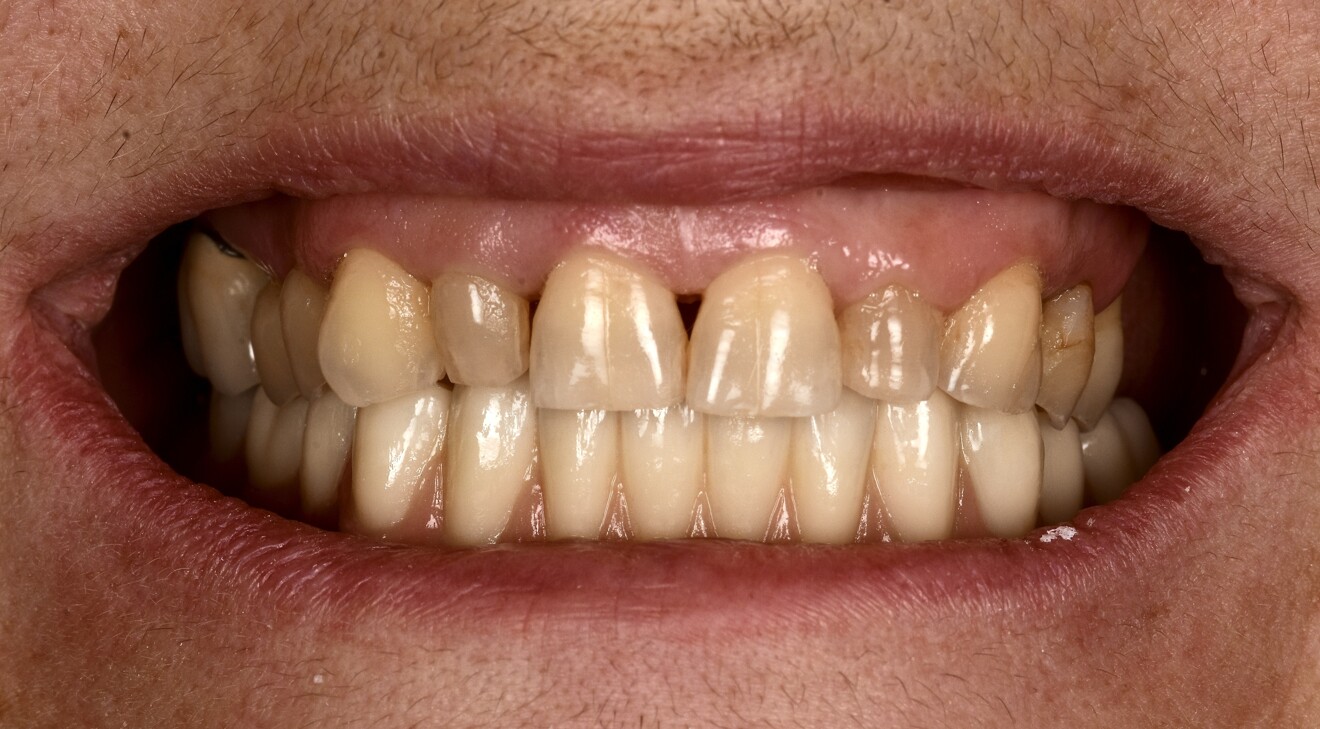

A 65-year-old female patient presented with complaints of tooth sensitivity under her existing mandibular prothesis and expressed concern over her missing teeth and periodontal health. The patient also inquired about the feasibility of implants to restore function and aesthetics.

Intra-oral examination revealed compromised mandibular dentition, an old fixed prothesis, missing posterior teeth on the left side, periodontal involvement and gingival inflammation. A panoramic radiograph was obtained, and the findings were reported to the patient (Figs. 1a & b; 2a & b). Both mandibular canines had visible periapical radiolucencies. A CBCT scan was performed for a more detailed assessment of the alveolar bone anatomy (Figs. 3a & b). Temporomandibular joint examination revealed no indication of dysfunction (crepitus, clicking or pain).